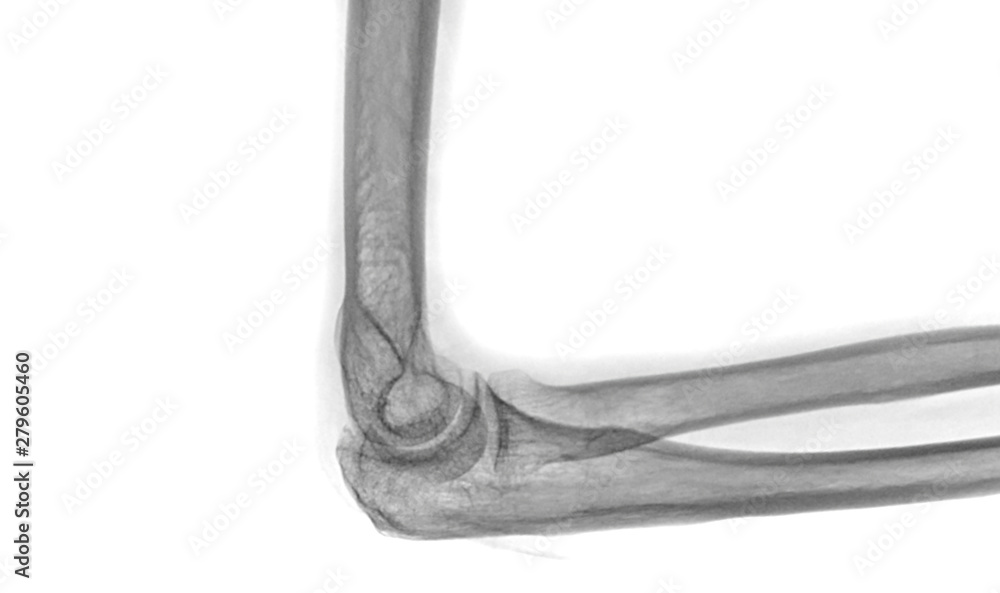

Right Elbow X-Ray . Check the anterior humeral line:. This elbow radiograph series represent a. Normal bones and joint alignment. Your elbow bones include the upper bone of your elbow joint (humerus) and the lower bones of. On “anatomical parts” you can choose between two types of labels: The traumatized elbow is discussed above. the elbow series is a set of radiographs taken to investigate elbow joint pathology, often in the context of trauma. In young athletes, osteochondritis dissecans (ocd) and apophysitis should be considered.